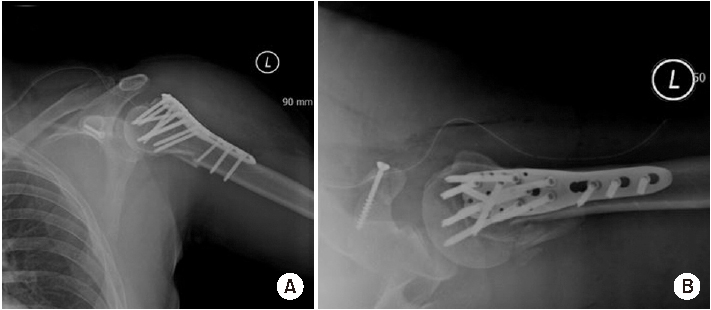

Shoulder joint dislocation has the most common incidence rate compare compared to other joints. It is reported that shoulder Shoulder dislocation couldmay be associated with glenoid rim, greater tuberosity of humerus and coracoid process fracture. There were have only been 2 cases of anterior shoulder dislocation simultaneously combined with simultaneous glenoid rim, coracoid process, and humerus greater tuberosity fracture worldwide and no report reports in Korea. We present a case of quadruple fracture (glenoid rim, coracoid process, greater tuberosity, surgical neck of humerus) associated with anterior shoulder dislocation and treated successfully by open reduction. In addition, with we provide the injury mechanism, diagnosis, treatment procedure and discussion.